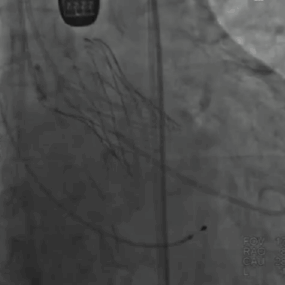

主动脉根部造影显示瓣上重度环状钙化轻中度反流,冠脉灌注良好